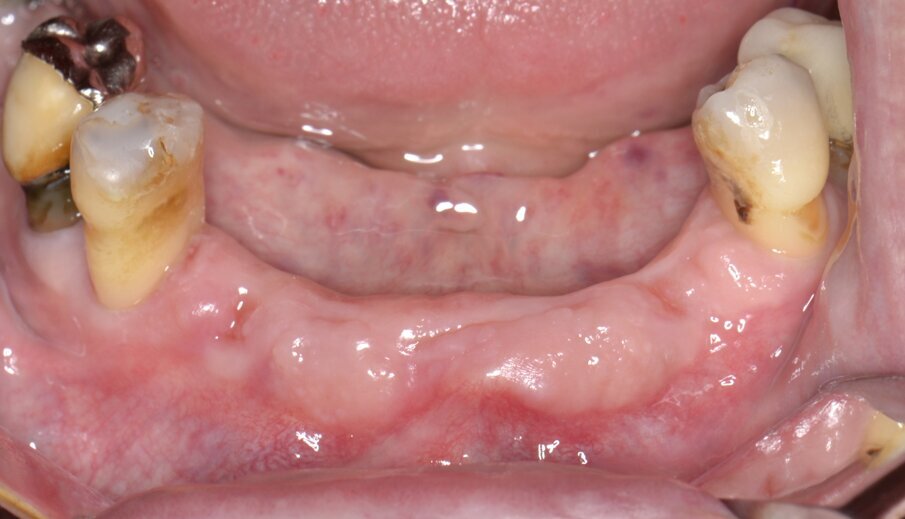

Fig. 1 - Immagine preoperatoria dell’area edentula.